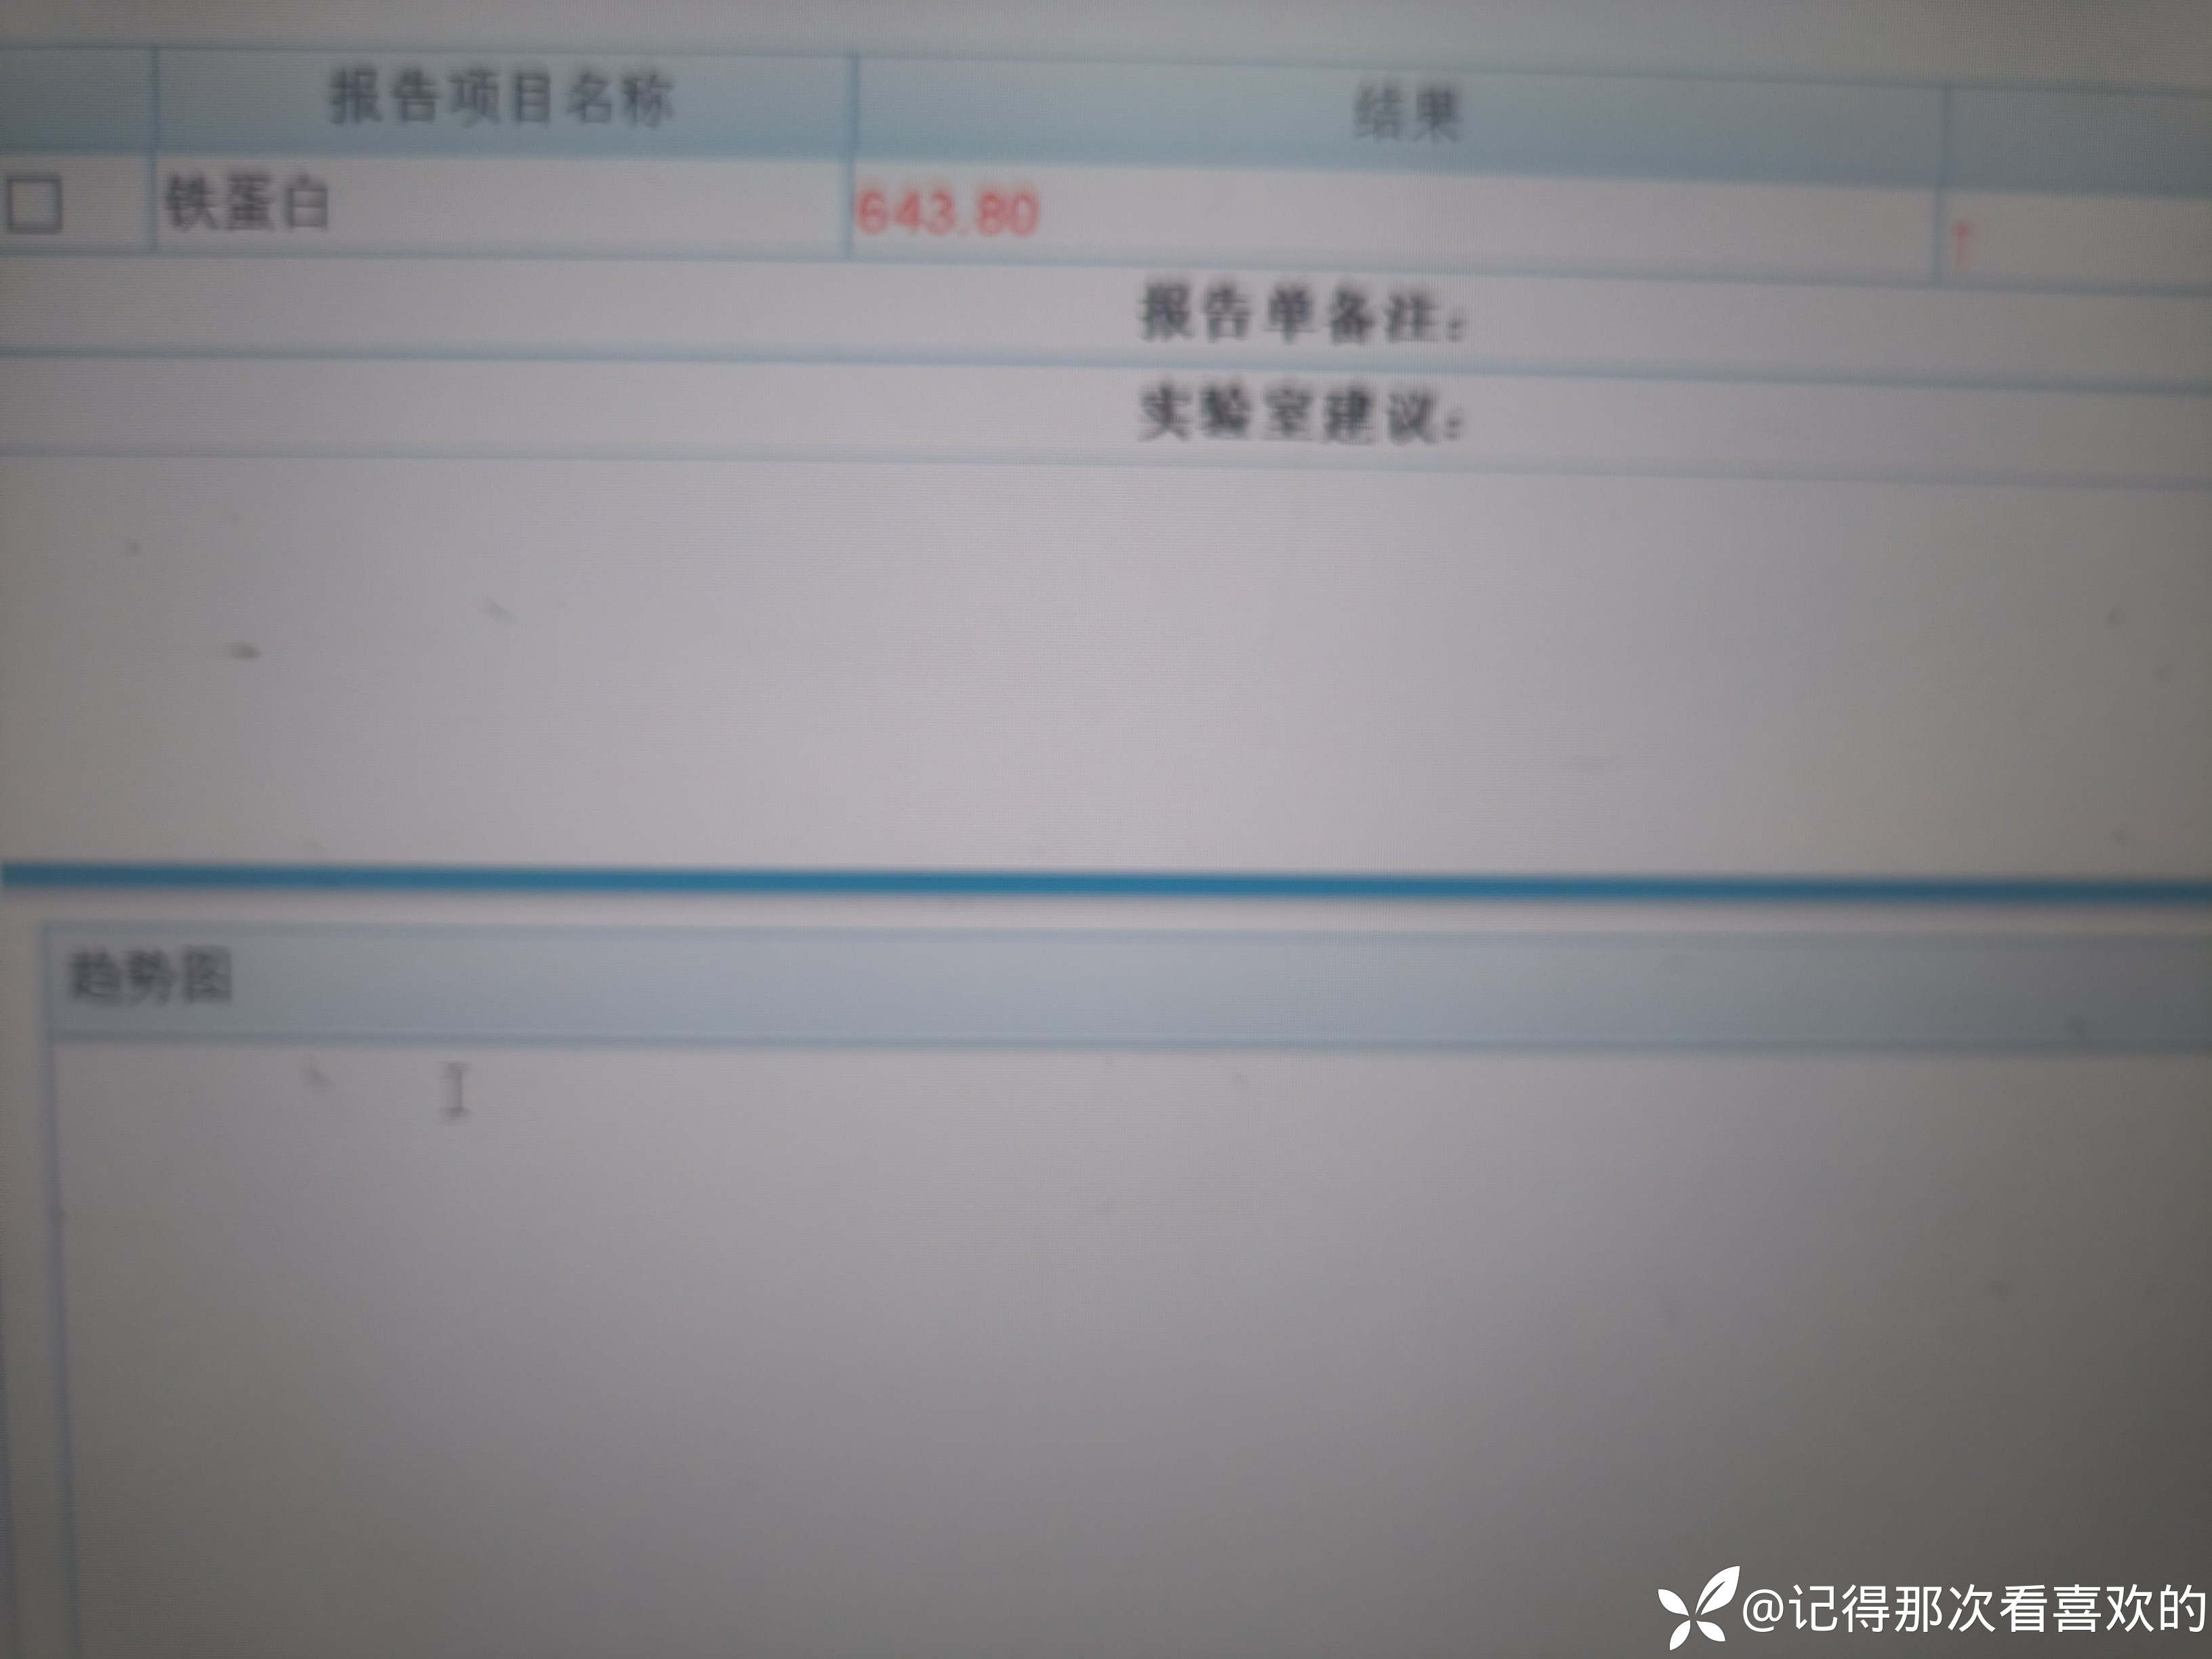

病例特点:患者钟某 男,14岁,以"髋、膝、足肿痛1年余,加重3日。"为主诉入院。现病史:缘于1年前无明显诱因出现左侧髋关节、双足跟、左踝关节、右足第一足趾关节肿胀、疼痛, 疼痛呈持续性,多于阴雨天、活动后症状加重,疼痛未向他处放射、转移,症状严重时行走困难。遂就诊于我科,查"HLA-B27(+)、CRP 70mg/L、骶髂MR:骶髂关节肿胀",诊断为"强直性脊柱炎",先后予皮下注射"司库其尤单抗150mg qw、阿达木单抗40mg q2w",上述症状较前好转,此后不规律用药,于半年前自行停用上述药物,未再规律随诊。3日前再发左膝、双肘关节肿痛,性质同前,程度较前加重,影响行走,伴有发热,体温最高达39℃,自行服用退烧药(具体不详)后体温较前下降,上述关节肿痛无明显改善。现为求进一步治疗,就诊我院,门诊拟"强直性脊柱炎"收住入院。体格检查:T36.6℃ P138次/分 R50次/分BP/120/68mmHg 专科情况:生命征平稳,神志清楚,双肺呼吸音清,未闻及干湿啰音,心律齐,各瓣膜听诊区未闻及杂音,全腹软,无压痛及反跳痛,未触及包块,双肘、左膝关节肿胀、压痛、触之皮温高。双下肢无浮肿,病理征未引出。

诊疗计划:1.入院予二级护理,监测血压、脉搏、呼吸。2.入院完善三大常规、凝血、生化、骶髂MR、彩超、CT、心电图等相关检查评估病情。3.治疗上暂予抗炎镇痛,辅以护胃治疗,待相关检查结果回报后进一步治疗,本次就诊拟行生物制剂治疗,予完善骨保护药物,传染病相关检查排除禁忌症,患者本次发病伴有发热达39℃,追问病史患者诉偶有干咳不适,目前已改善,予完善呼吸道病原学检查明确病情。4.患者Padua评分1分,属于发生VTE低危风险,实行VTE基本预防,动态评估Padua评分。5.已将目前病情及现有临床诊断以及存在疾病复杂性、个体的差异性、对治疗的反应不同、鉴于目前医学技术水平有限,和下一步相关诊疗详细充分告知患者家属,取得家属的理解并同意配合下一步诊疗及检查。6.NRS-2002评分3分,目前患者营养状态尚可,进食情况尚可,根据病情变化动态评估。